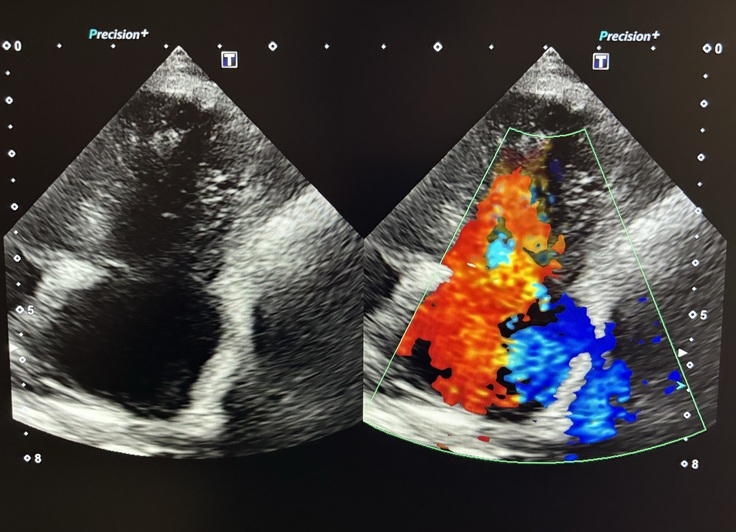

急いで近くの病院に連れていくと、肺に水が溜まっているので薬と注射で水を抜きますと言われました。

命の危機が迫っています!僧帽弁閉鎖不全症・三尖弁閉鎖不全症